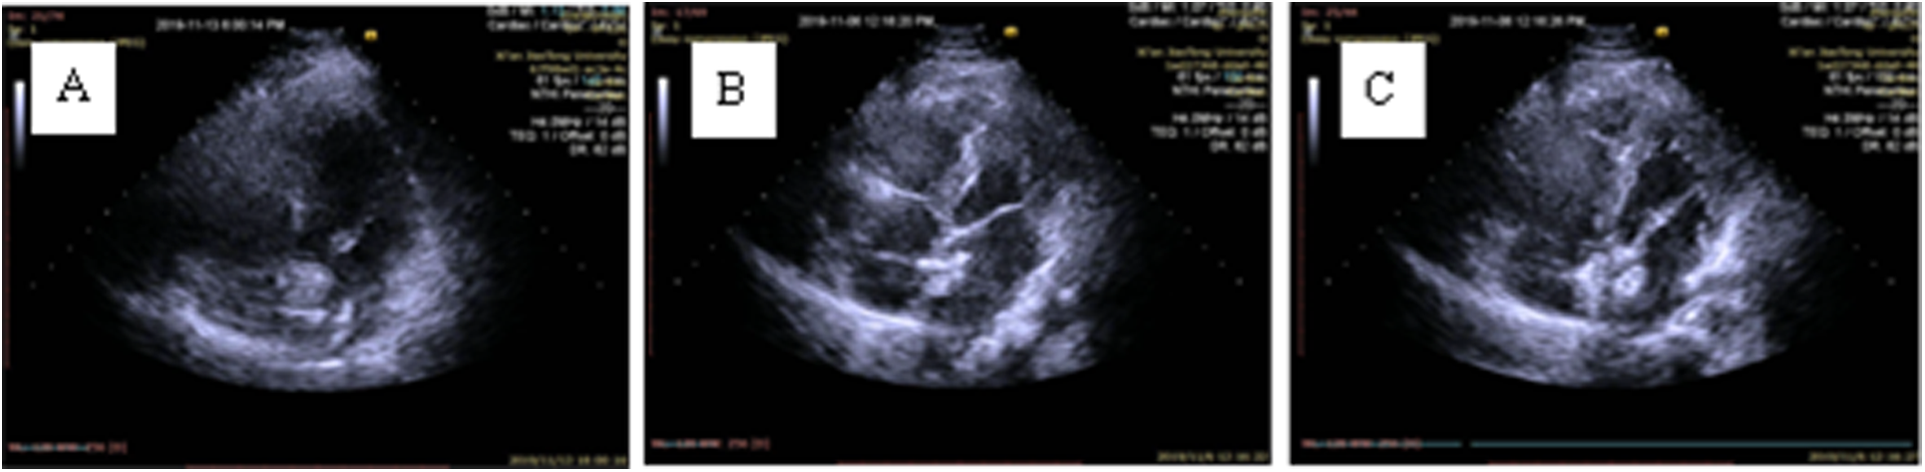

Figure 4

The release process of the occluder under TTE guidance. (A) The left disc is deployed in the left atrium; (B) The left disc gradually fits the interatrial septum (IAS); (C) The right disc is released.